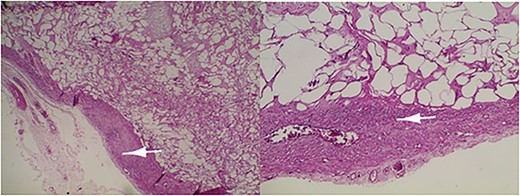

Microscopic examination revealed a benign mesenchymal proliferation of fasciculated architecture within a chondromyxoid background (Fig. 3). In addition, focal areas of chondroid metaplasia were also identified (Fig. 4). On immunohistochemical analysis, the smooth muscle cells expressed desmin, h-Caldesmon, and vimentin ( Figs 5 and 6). The Ki-67 proliferation index was low.

Lipoleiomyoma: proliferation consisting of a smooth muscle component visible in the periphery (arrow) and mature adipocytes separated by fibrous trabeculae. Haematoxylin and eosin; ×10.

Immature or mature cartilage nodules identified in conjunction with adipocytes and smooth muscle bundles. Haematoxylin and eosin; ×20.